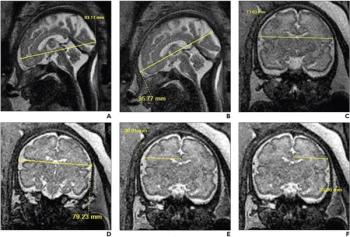

Researchers found that in utero opioid exposure resulted in seven out of 14 2D biometric measurements of the fetal brain being smaller on magnetic resonance imaging (MRI) scans in comparison to fetuses without opioid exposure.